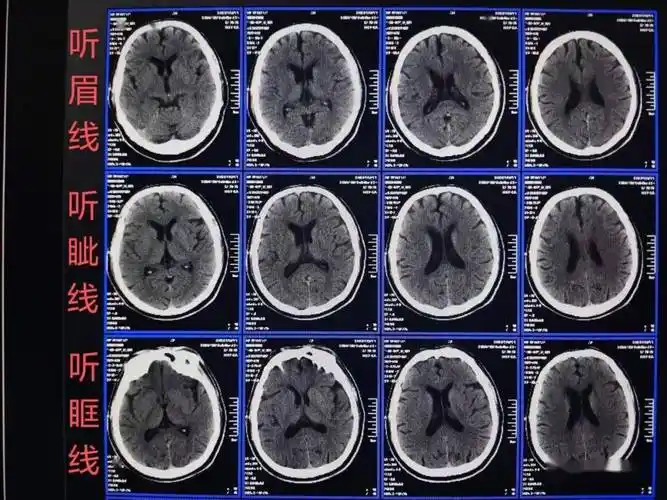

皓月ct头颅图像技术和样片分享

影像总结头颅ct基本知识与常见病变

急诊头颅ct3b阅片法这个阅片法值得推荐